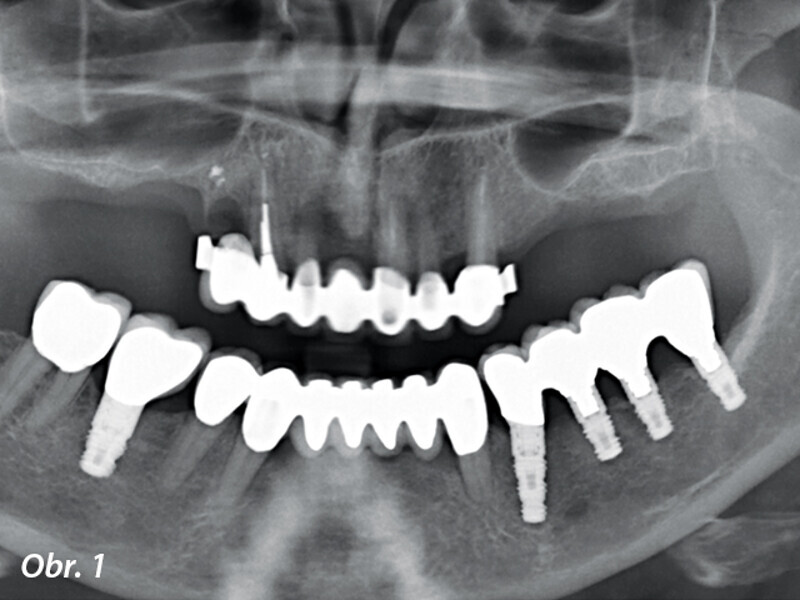

CBCT kostní denzitometrie pro rozhodování před chirurgickým zákrokem